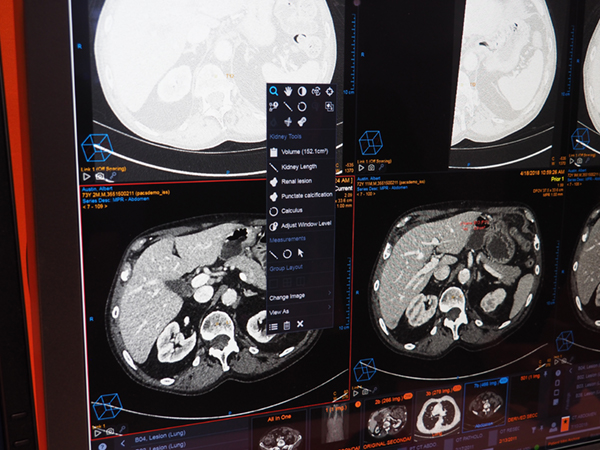

診断補助(Diagnostic Aide)として,腹部領域でCTのアキシャル画像から臓器のセグメンテーションと自動認識を行う。肝臓や腎臓といった臓器を自動で判別し,その臓器に合った測定ツールを提示する。腹部の病変の自動抽出と計測を行い,計測結果は自動でレポートシステム(Vue Reporting)に反映される。レポートのテキストはハイパーリンクとなっており,ビューワの病変部とのリンクがつけられるほか,計測データはダイナミックに変化する。

Diagnostic Aide(W.I.P.)。臓器のセグメンテーションと自動認識を行い測定ツールを表示。

Diagnostic Aide(W.I.P.)。腎臓を自動認識して臓器に合わせた測定ツールが表示されている。